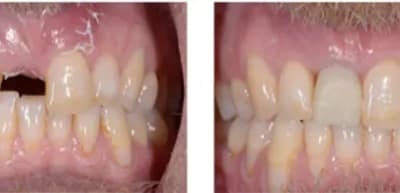

A Recent Case Study on Dental Implants

Our patient was presented in 2015 with an old front crown which was made with old dental technology. He had an injury to the tooth 20 years prior and had root canal treatment and a crown. It had a...